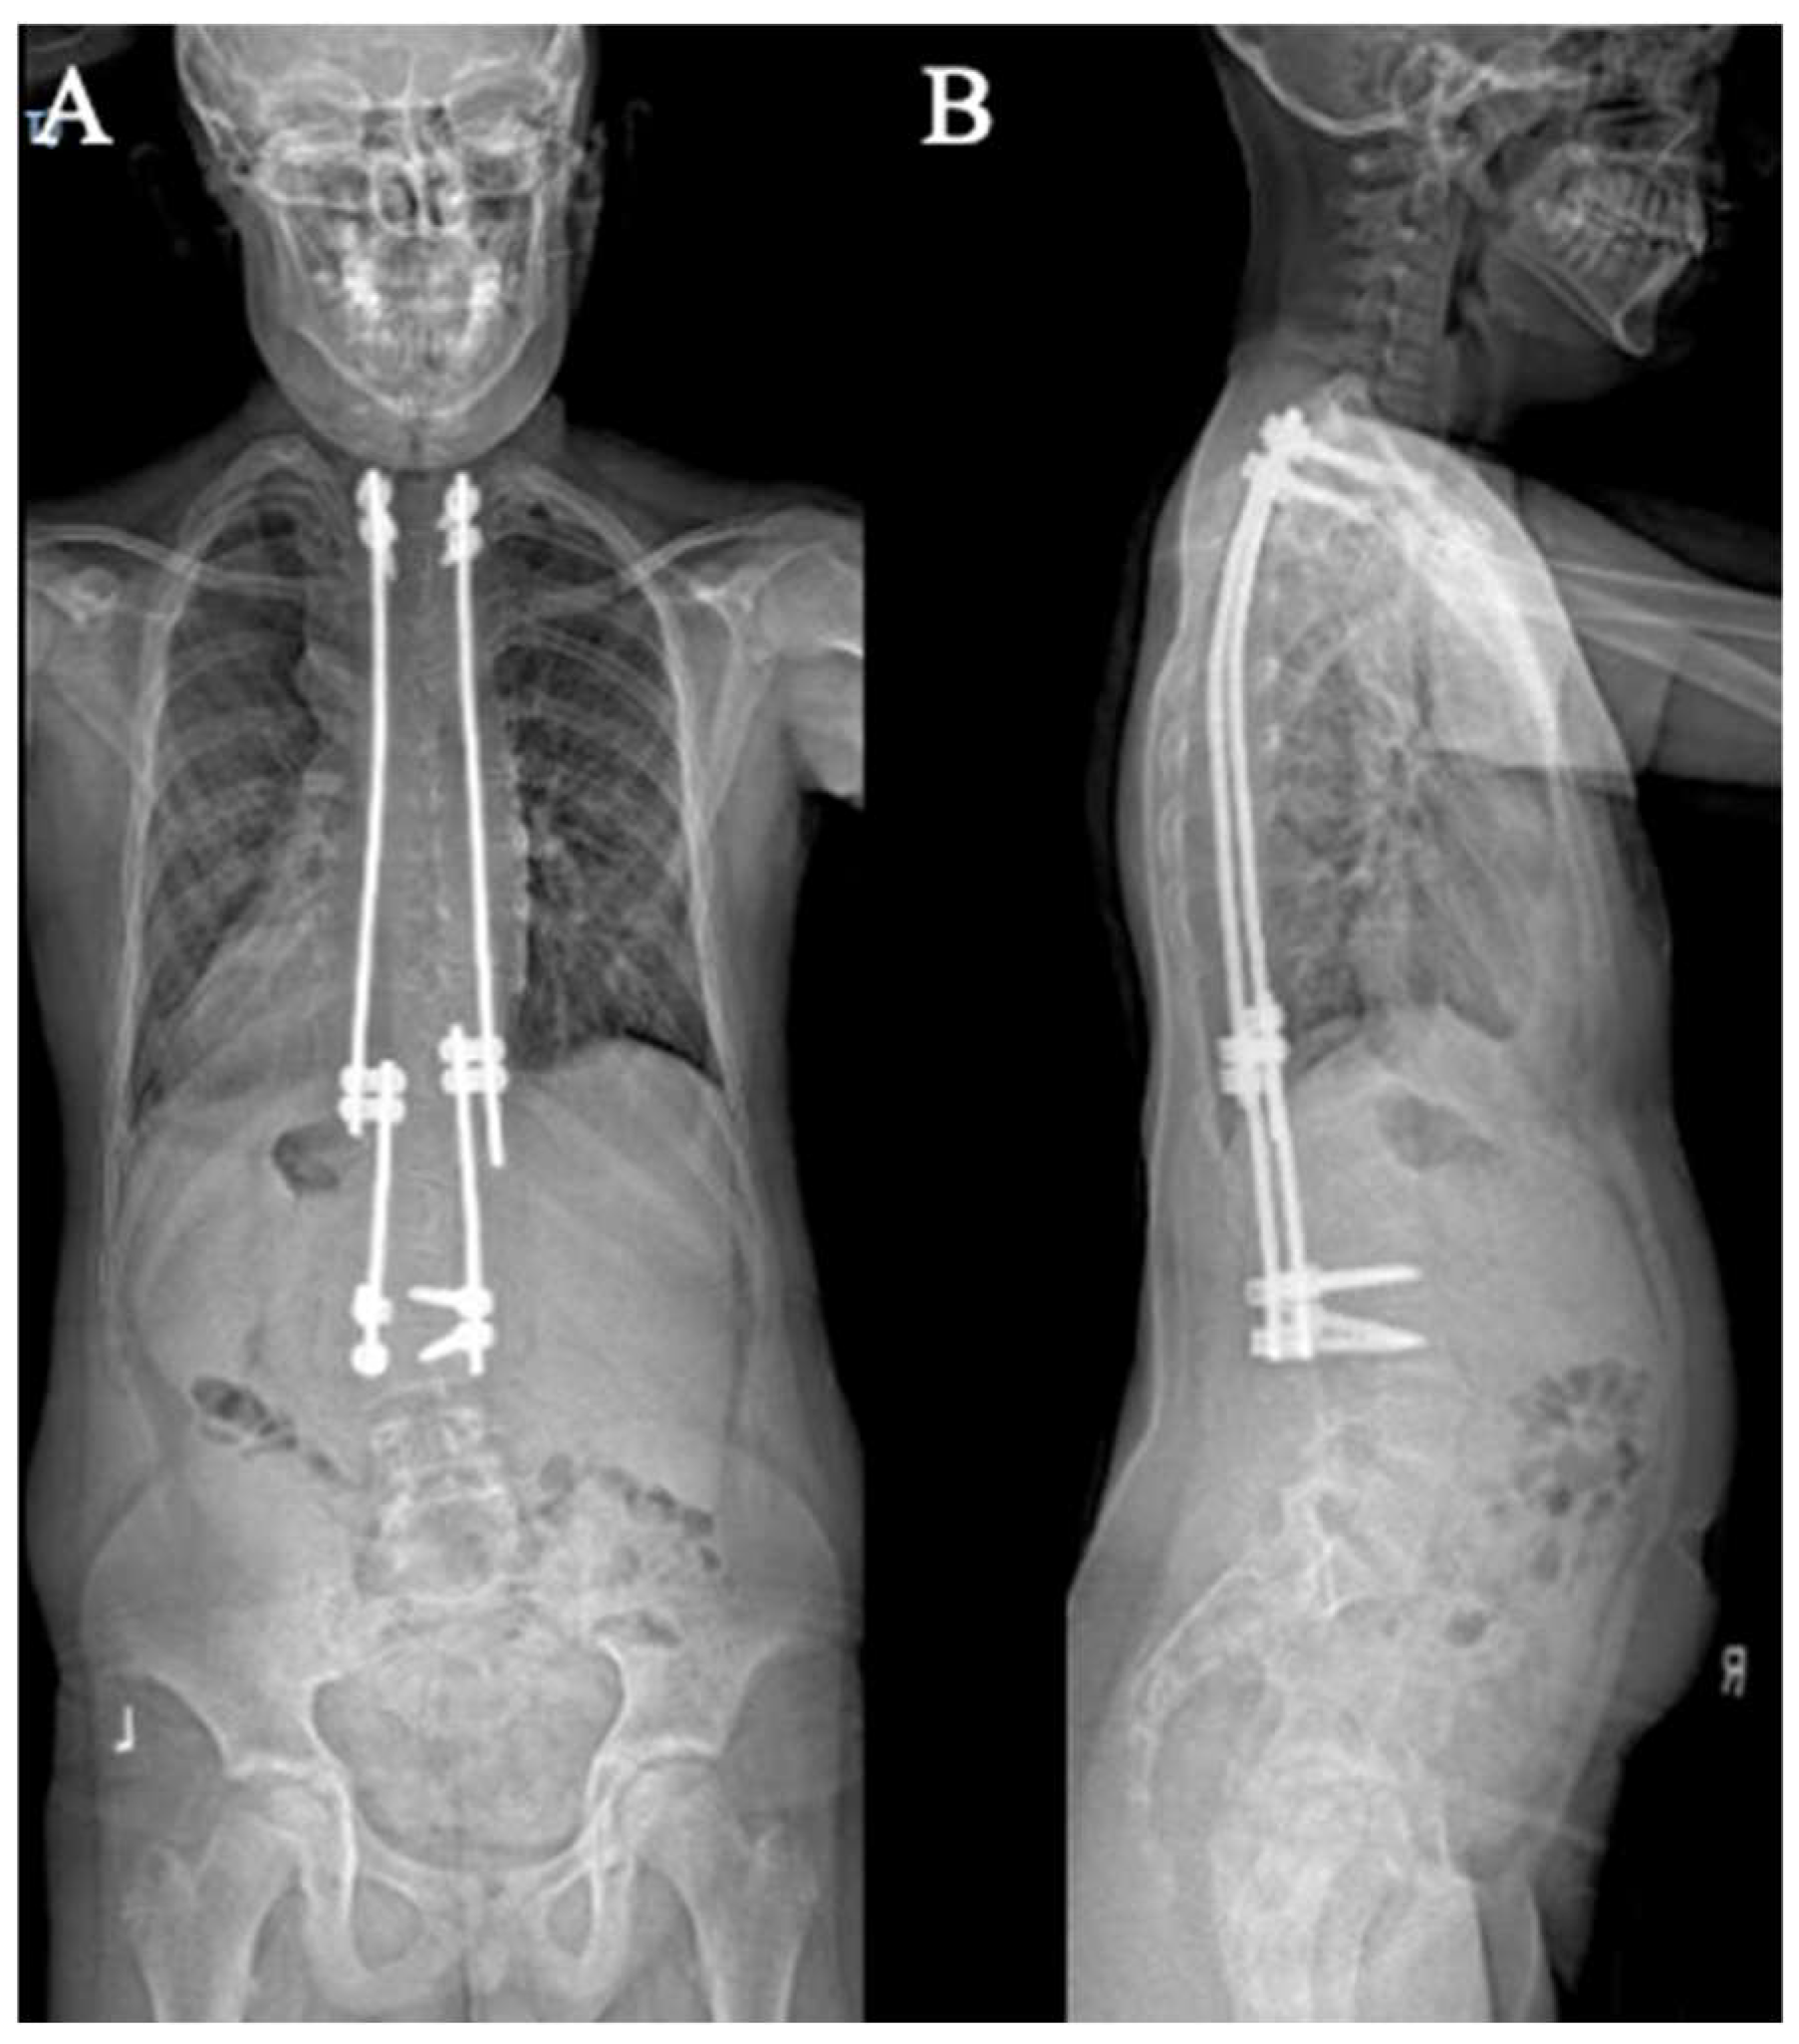

3.3. Traditional Growing Rods

The construct-to-construct internal distraction technique is the most common configuration for traditional growing rod constructs (Figure 6). The distal anchor points comprise two-level pedicle screw fixation. The last spinal level will represent the lower instrumented vertebra of the final fusion construct. The proximal anchor points may be either upgoing rib hooks or pedicle screws. We prefer pedicle screw fixation at upper instrumented vertebra, upper instrumented vertebra-1, and occasionally upper instrumented vertebra-2. It is important to keep in mind that these proximal pedicle screws will experience significant distraction forces with serial lengthening that could loosen the screws at the time of the final spinal fusion. A long titanium rod is passed under the muscle layer to engage into the proximal anchor points. The distal segment of this rod is connected to a lateral domino connector with significant overlap to allow for serial distraction in the future. A shorter rod is tunneled through the domino connector and engaged to the distal anchor points. A rod gripper is used to engage the longer, proximal rod approximately 1 cm above the domino connector (Figure 3). The set cap on the domino connector is loosened, and a distractor is placed between this connector and the rod gripper. Gradual distraction is applied in a controlled, “click-by-click” manner before the set cap is tightened to hold the correction.

Figure 6. AP (A) and lateral (B) X-rays demonstrating the construct-to-construct internal distraction technique in a traditional growing rod construct.